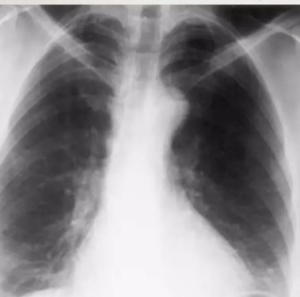

• ⁠ ⁠Xray showing cavitatory consolidation in right upper lung zone and multiple ill-defined nodules in both lungs

CAVITATION AND TREE IN BUD SIGN IS INDICATIVE OF AN ACTIVE DISEASE PROCESS AND USUALLY HEALS S A LINEAR OR FIBROTIC LESION.